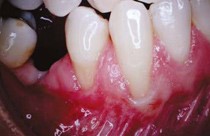

APRES :

Ces types d'interventions permettent des décollements minimums et donc des suites opératoires quasiment indolores

- Sensibilité au chaud et froid

- Aspect de dent longue

- Traitement préprothétique afin de maintenir les gencives sur le long terme